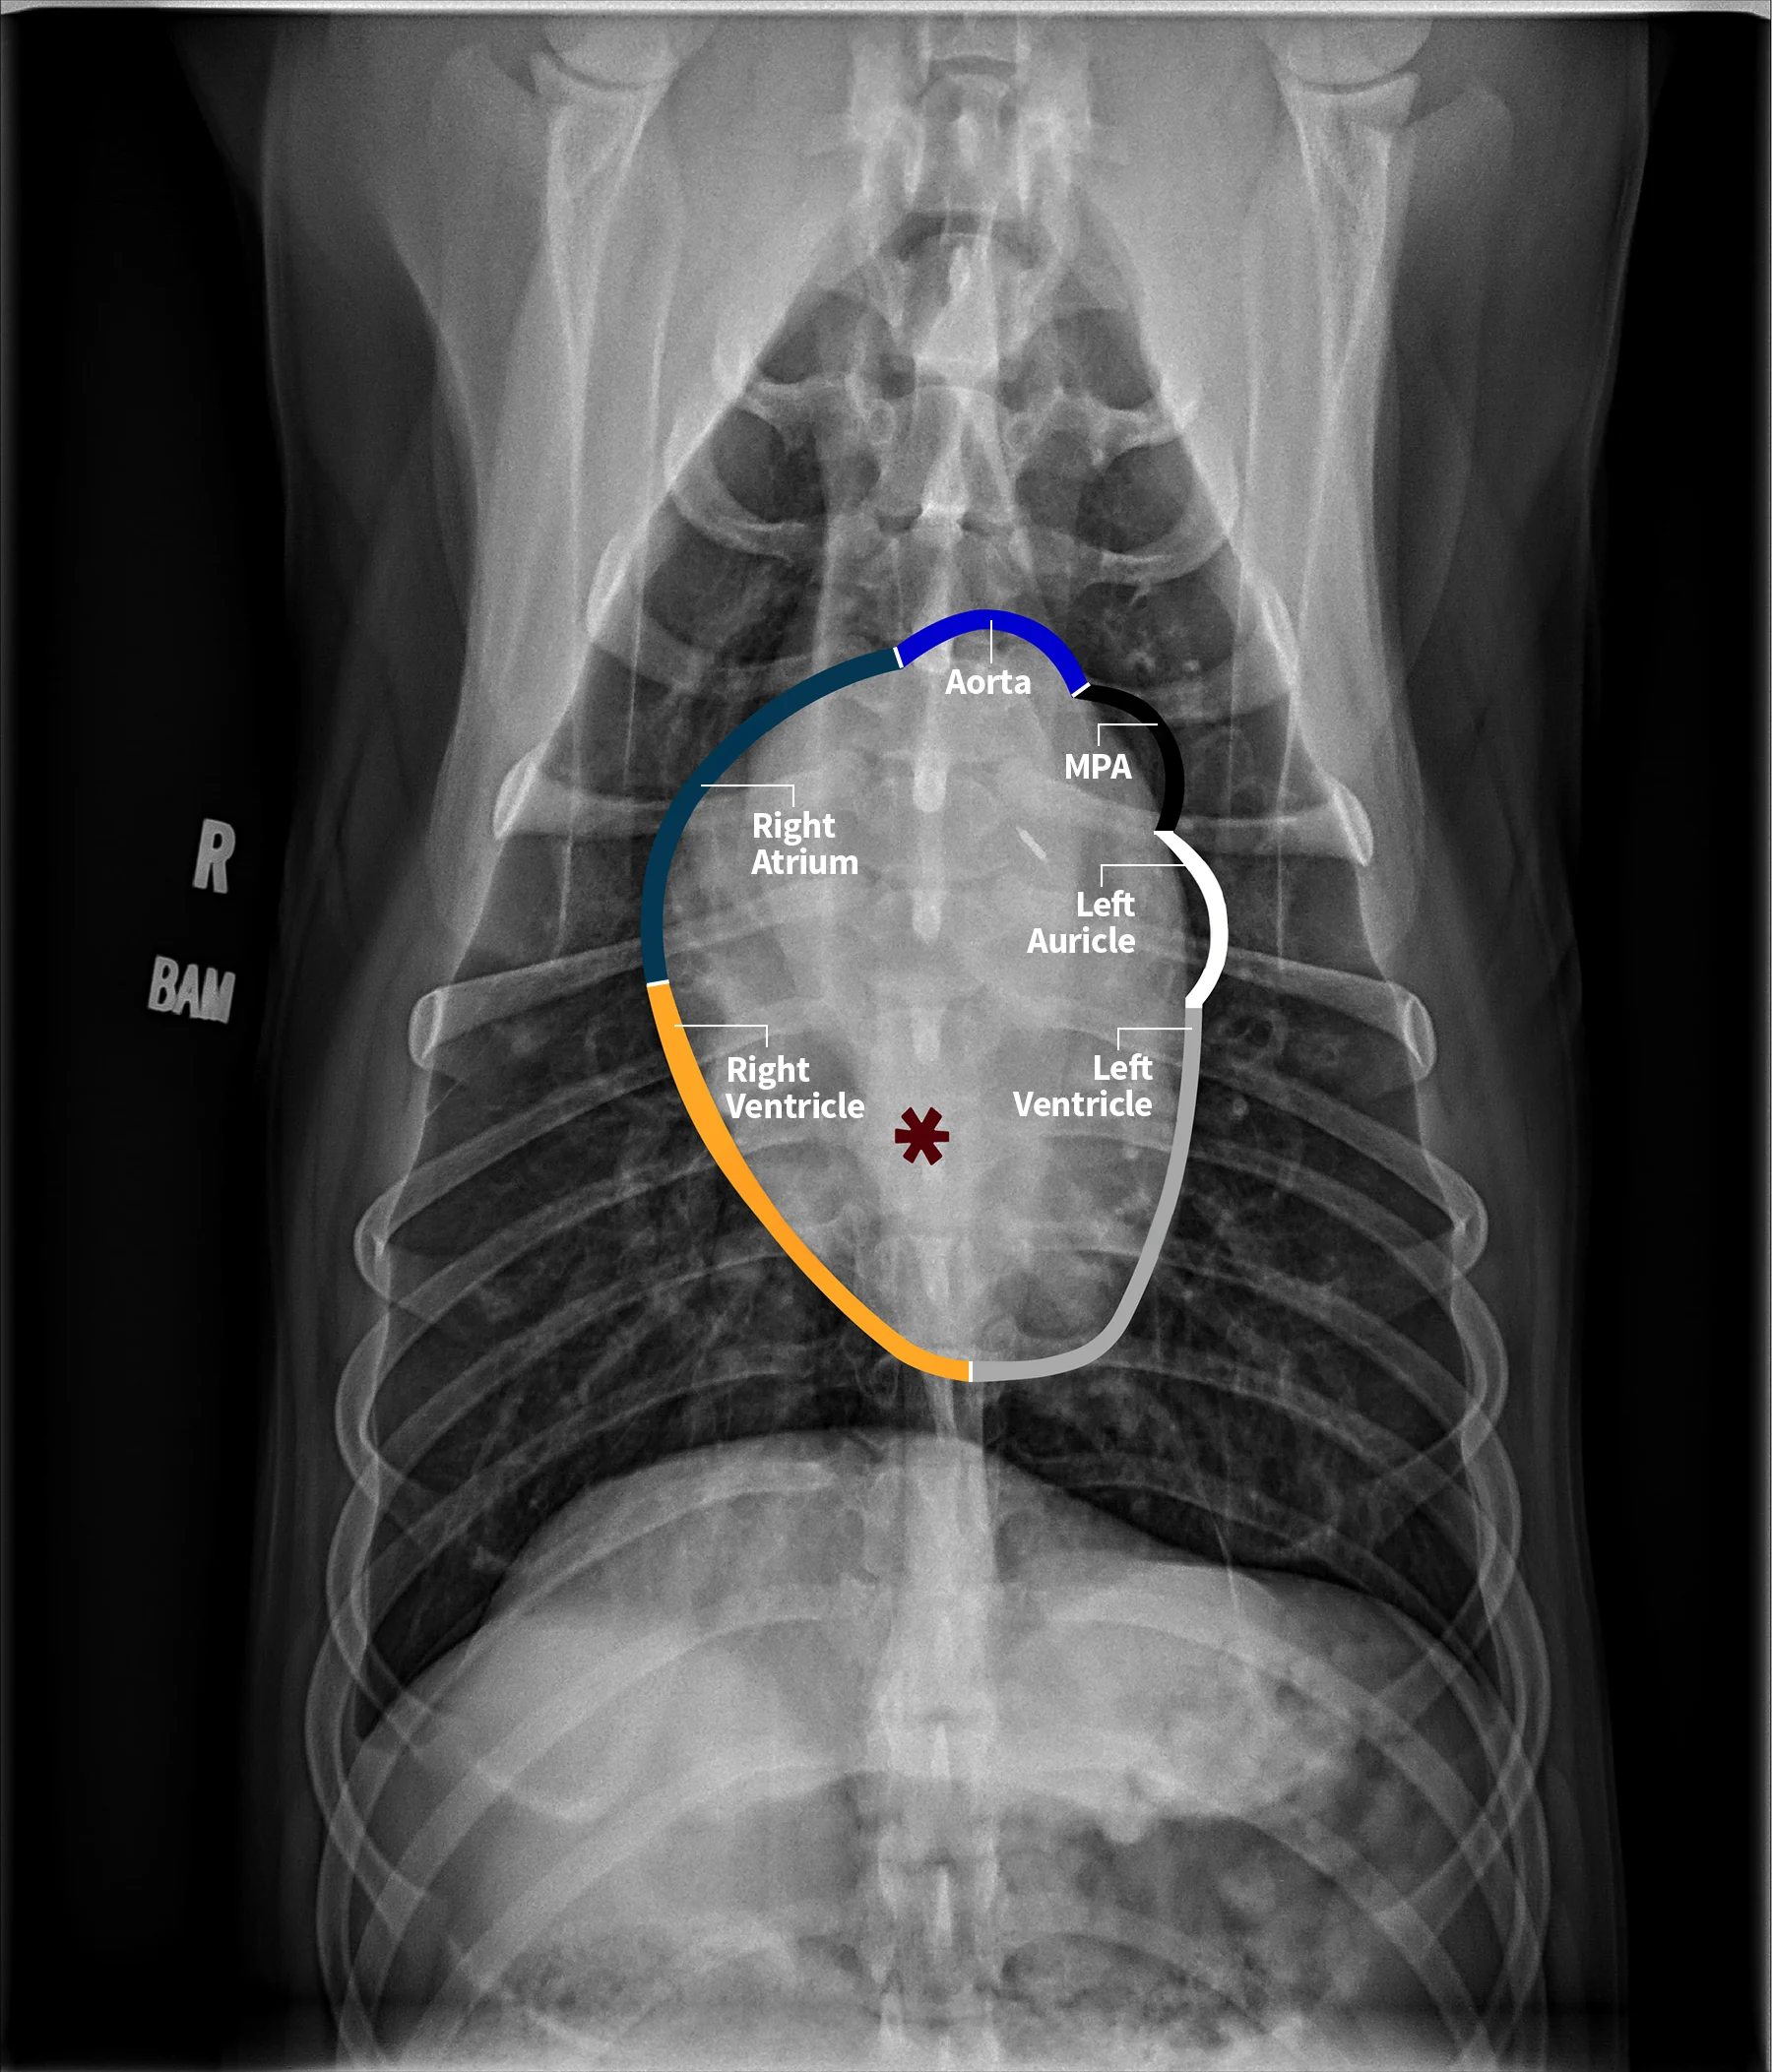

The cardiac silhouette should be evaluated systematically. Using the clockface analogy when evaluating DV or VD projections, the apex of the heart is located at ≈5 o’clock, and the right ventricle is in the region between 5 and 6 o’clock to 9 o’clock, followed by the right atrium, aortic arch, main pulmonary artery (MPA), left auricle, and left ventricle (Figure 4). A similar approach can be followed when evaluating the heart in a lateral projection. The terms cranial and caudal waist or borders are used to describe regions of the cardiac silhouette (Figure 5). Changes within particular regions can indicate which structure is likely abnormal and highlight potential underlying disease processes.

FIGURE 4 Normal VD projection in a large-breed dog showing regions of the cardiac chambers. Orange, navy blue, royal blue, black, white, and gray borders indicate region locations of the right ventricle, right atrium, ascending aorta, MPA, left auricle, and left ventricle, respectively. Abnormalities of the great vessels or auricles would result in focal bulges in their respective regions (not present in this image). The left atrial body (asterisk) can be seen. Illustration courtesy of Jose Narvaez Perez